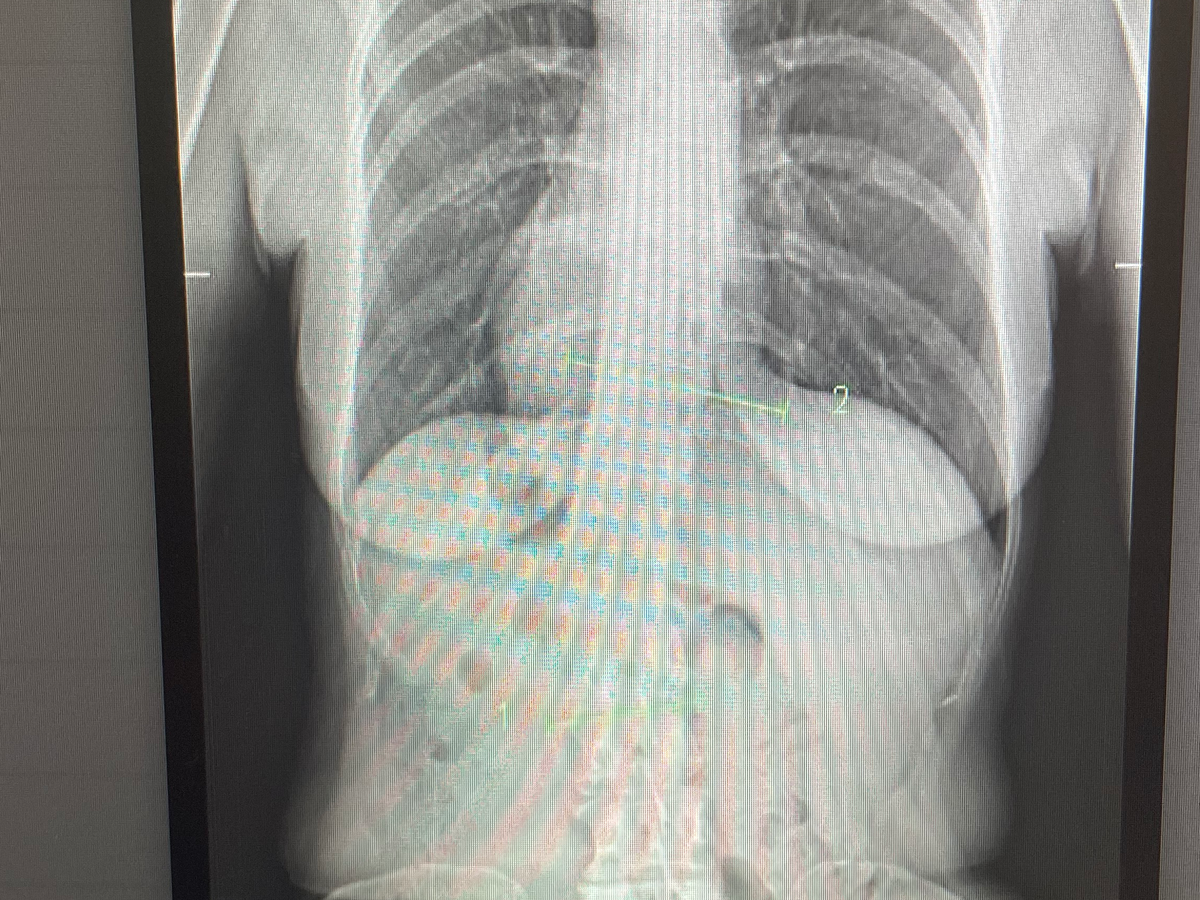

My name is Marilyn and I suffer from fibromyalgia and scoliosis. Today I ordered my scoliosis brace from my specialist and I have a lot of out of pocket treatments to pay for. I hope that will help the chronic pain that I live with on a daily basis. Any help would be appreciated. My brace is $4500 Australian.